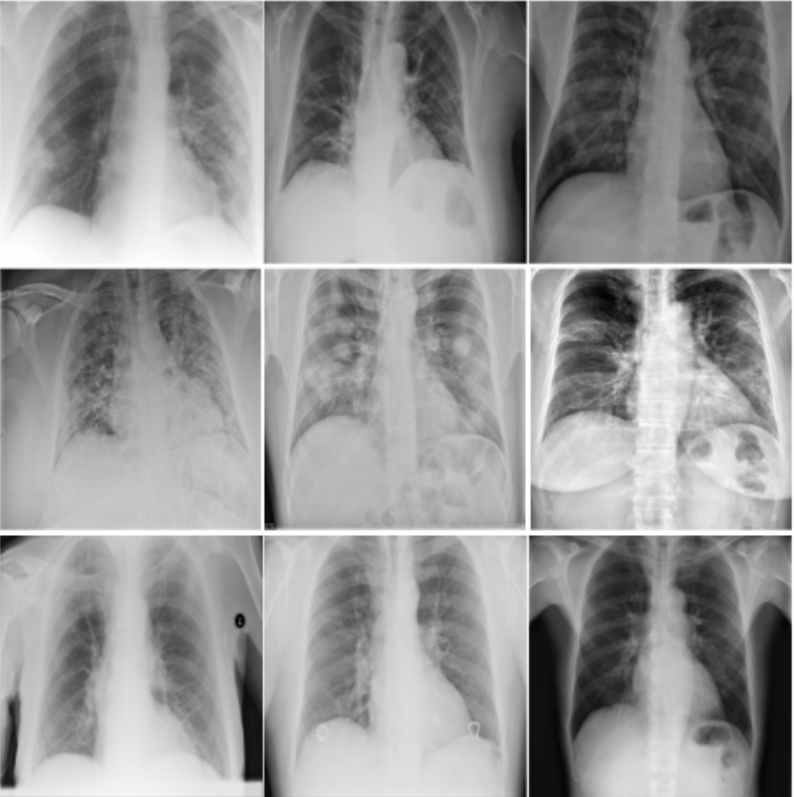

Covid19

Covid 19 Cxr Appearance